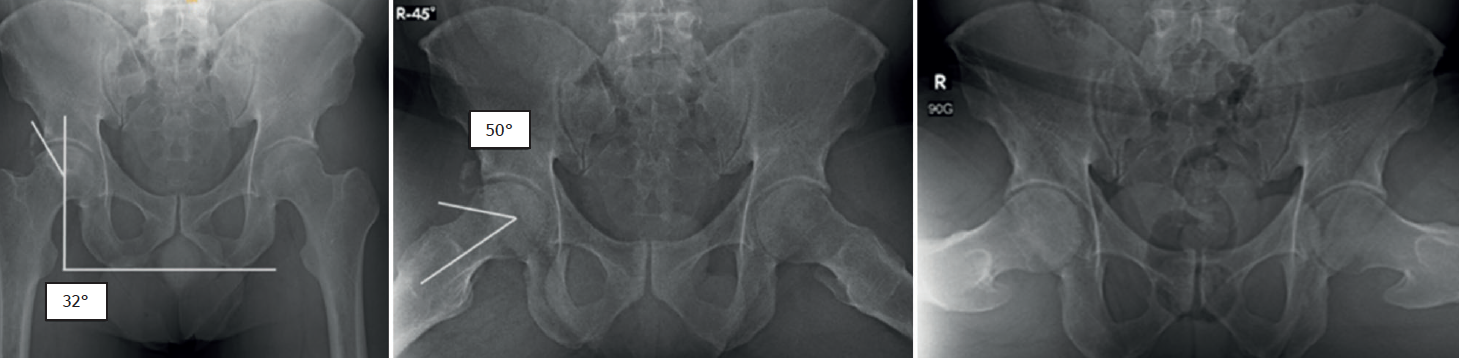

Se trata de un paciente masculino de 45 años, sin antecedentes clínicos de importancia. Acude por dolor en la cadera derecha sin causa, que incrementa con la actividad física, la bipedestación y la sedestación prolongada. A la valoración presenta flexión de 120° dolorosa, extensión de 30°, abducción de 40° dolorosa, aducción de 30°, rotación interna de 15° dolorosa y rotación externa de 25° dolorosa; maniobras: FABER +, FADIR + y log roll +; escala funcional médica Hip Outcome Score (HOS) de 35/68 (51,5%) puntos y escala visual analógica (EVA) del dolor de 7/10. En la radiografía anteroposterior de pelvis y en posición de Dunn a 90° se evidencia esclerosis de la cabeza femoral, además de morfología de tipo cam y pincer (Figura 1). En la artrorresonancia magnética de la cadera derecha, se evidencia una imagen hipointensa en la secuencia T2, con bordes hiperintensos en la secuencia T1 (signo de doble contorno), desgarro del labrum acetabular de Czerny-Hoffman(8) IIIA, adelgazamiento de cartílago articular, sin colapso de la cabeza femoral. El ángulo de Kerboul(9) medido es de 284° con alto riesgo de colapso de la cabeza femoral (Figura 2).

Figura 1. Radiografía anteroposterior (AP) de pelvis y proyección de Dunn a 90°, evidenciando un ángulo centro borde (Wiberg) aumentado de 50° y un ángulo alfa aumentado de 60°.